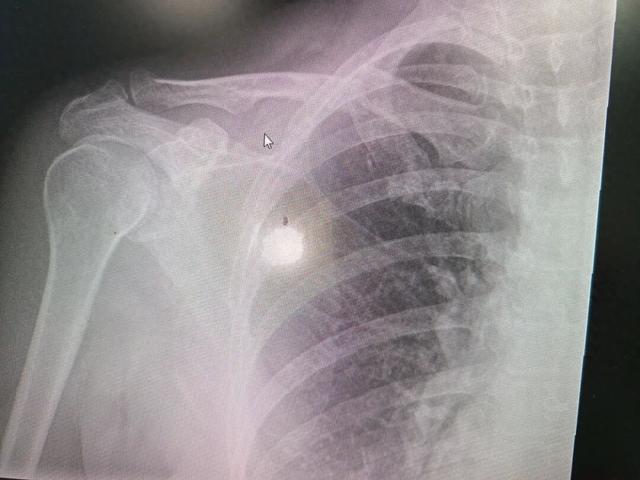

多发性骨髓瘤的疾病特征与诊断 - 多发性骨髓瘤是一种起病隐匿、善于伪装的血液系统疾病,被称为“吃骨头的血液病”,极易被误认为是普通衰老或常见慢性病[7] - 疾病进程分为两个阶段:第一阶段,骨髓瘤细胞异常增殖挤占正常红细胞生存空间,导致造血功能受损,临床表现为乏力、面色苍白等贫血症状,此时骨骼破坏尚未形成,是介入治疗的最佳窗口期[5];第二阶段,肿瘤细胞分泌破坏骨骼的因子,导致严重的溶骨性破坏,骨骼在轻微外力下即可发生病理性骨折[6] - 确诊案例显示,患者血红蛋白仅为58g/L,属于重度贫血,并伴有右侧锁骨病理性骨折[2];实验室检查发现γ球蛋白为27.5 g/L,显著高于8.0-15.8 g/L的参考区间,同时M蛋白含量为18.0 g/L[5] 关键症状组合与筛查警示 - 对于40岁以上人群,若出现长期无法纠正的贫血,应拓宽筛查思路,警惕血液系统疾病[7] - 需特别警惕的三种症状组合包括:第一,贫血伴随骨痛或病理性骨折,例如无明显外伤仅因轻微动作(如举扫把)就发生骨折[2][7];第二,贫血伴随泡沫尿久久不散或眼睑、下肢浮肿,原因是肿瘤产生的异常免疫球蛋白轻链损伤肾脏肾小管[8][9];第三,贫血伴随反复感染,如频繁感冒、发烧、肺炎,原因是正常免疫球蛋白减少导致身体免疫屏障受损[10][11] - 在未排除骨髓瘤骨破坏前,应避免对伴有骨痛的患者进行大力推拿,以免加重骨折风险[7] 诊断建议与治疗前景 - 建议对长期贫血、乏力的患者进行正规医学检查,关键诊断线索可通过血常规、肝肾功能、电解质(尤其是钙离子)及免疫球蛋白检测获得[13] - 随着靶向药物、免疫疗法等不断进步,多发性骨髓瘤已进入慢病化管理时代,早期发现并规范治疗可使患者获得良好的生存质量[13] - 年前大扫除期间中老年人活动量增加,是骨折高发期,需更加关注身体信号[12]